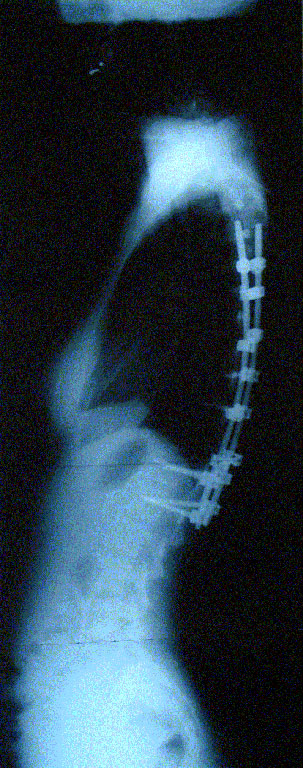

Grafilerle Skolyoz